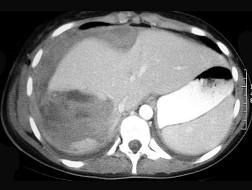

问题 处理肝外伤哪一项是不正确的 ( )

选项 A、肝创面处要放置引流 B、严重广泛的肝组织损伤可行肝叶或肝部分切除 C、压动肝动脉有止血效果的可结扎肝动脉 D、失去活力的肝组织应予清除或切除 E、裂痕稍大的可用纱布填塞

答案 E